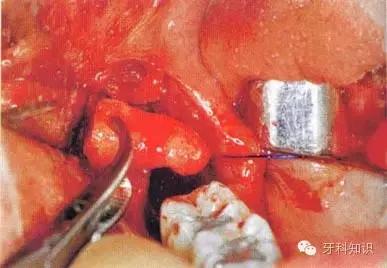

b翻瓣后,阻生牙的(牙合)面位于第二磨牙颈部及其牙槽嵴顶均清晰可见。切割牙体前先去除舌侧骨板以保护软组织

c使用纺锤形的车针( Komet - H162A.314),显露其最大周径至釉牙骨质界。车针末端应进入牙槽窝内壁

d 分牙前应认真确定分牙沟的位置:沿牙体长轴垂直(牙合)面至根分叉。用上述的车针分牙。切割至牙冠舌侧时应格外小心